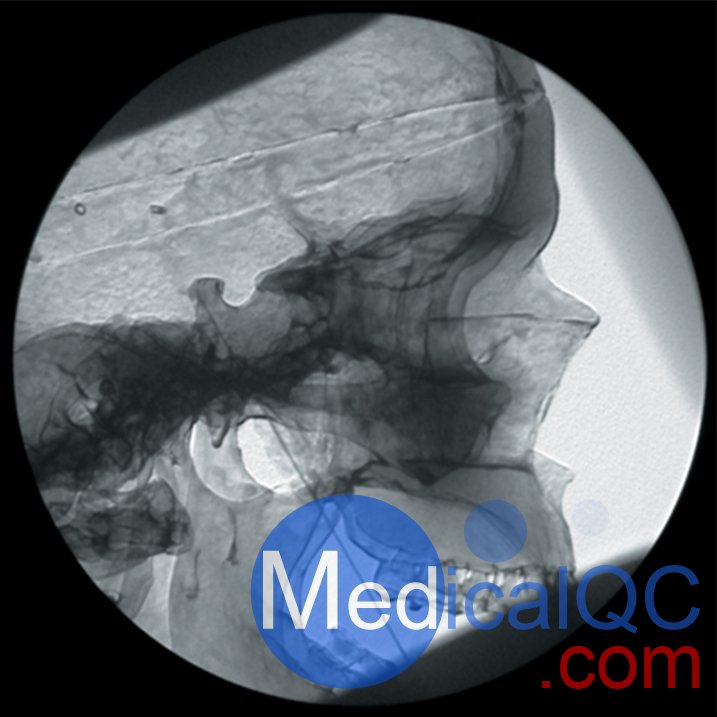

AR351脊椎穿刺模體,Adam,Rouilly脊椎穿刺模體是區(qū)域麻醉模擬人體模型,由曼徹斯特和索爾福德疼痛中心的顧問(wèn)麻醉師設(shè)計(jì)的,用于培訓(xùn)麻醉師正確放置神經(jīng)塊中的針頭以進(jìn)行疼痛處理。

應(yīng)用于個(gè)體神經(jīng)阻滯的表面解剖知識(shí)

圖像的方向和適當(dāng)?shù)纳渚€照相地標(biāo)的識(shí)別

針插入的識(shí)別點(diǎn)和方向角

識(shí)別與深骨結(jié)構(gòu)的接觸

拔針?lè)较蚋淖兘嵌鹊脑?br /> 模擬的終點(diǎn)是正確的射線照相外觀

需要精確的針頭放置以確保許多診斷性疼痛診所的功效,并且在使用神經(jīng)溶解解決方案時(shí)是必不可少的。放射線檢查以確認(rèn)應(yīng)放置針頭應(yīng)作為常規(guī)檢查,為此必須進(jìn)行實(shí)際培訓(xùn)

不熟悉該技術(shù)的受訓(xùn)人員嘗試進(jìn)行區(qū)域麻醉可能會(huì)給患者帶來(lái)不舒服和長(zhǎng)時(shí)間的手術(shù)

AR351脊椎穿刺模體,Adam,Rouilly脊椎穿刺模體可用于訓(xùn)練以下項(xiàng)目:

頸椎小關(guān)節(jié)注射

三叉神經(jīng)節(jié)阻滯或射頻針?lè)胖?br /> 腹腔神經(jīng)阻滯

AR351脊椎穿刺模體,Adam,Rouilly脊椎穿刺模體特點(diǎn):

人體模型由特殊涂層的塑料人體骨骼組成,頭部覆蓋著人造皮膚,軀干覆蓋著織物,受訓(xùn)人員可以在其上練習(xí)在X射線圖像增強(qiáng)器控制下放置針頭

人體模型的X射線密度低,因此減少了模擬程序中使用的輻射劑量